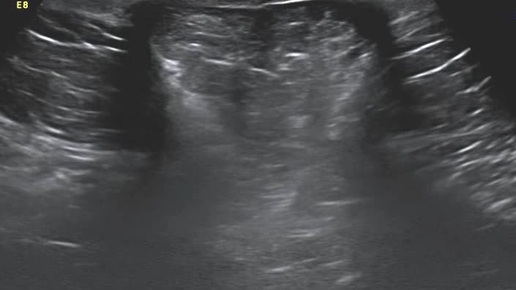

Видео к статье "Общие принципы ультразвуковой диагностики наружных грыж живота" Адрес: https://dzen.ru/a/Z2k58ScRsjQP-dA9